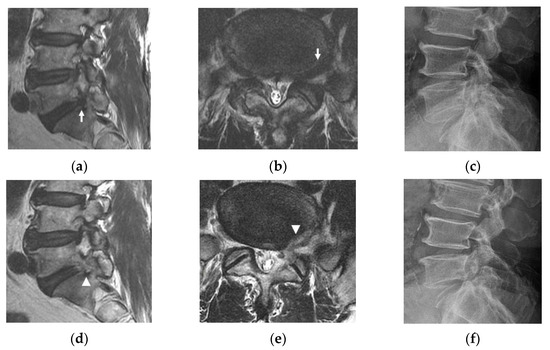

- Patients with L5 radiculopathy due to foraminal and extraforaminal stenosis at the L5-S1 level confirmed by MRI (Figure 1c,d).

- Patients with accompanying lateral recess stenosis at the same side with foraminal pathology, which simultaneously compress the L5 and S1 roots (Figure 1c,d).